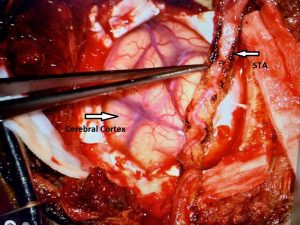

Noninvasive vascular imaging was sufficiently suggestive to warrant conventional digital subtraction angiography, performed by Dr. Brisman and confirming Moya-Moya syndrome (Figures 1). CT Perfusion (Figure 2) showed a decreased transit time of blood to the right hemisphere and the patient was recommended to undergo cerebral revascularization to avert stroke.

A right sided Encephaloduroarteriosynagios (EDAS) procedure was undertaken in which the right superficial temporal artery (STA) is sewn (synangiosed) to the pia in an effort to generate vascular arborization and increased blood flow to the hemisphere (Figure 3).